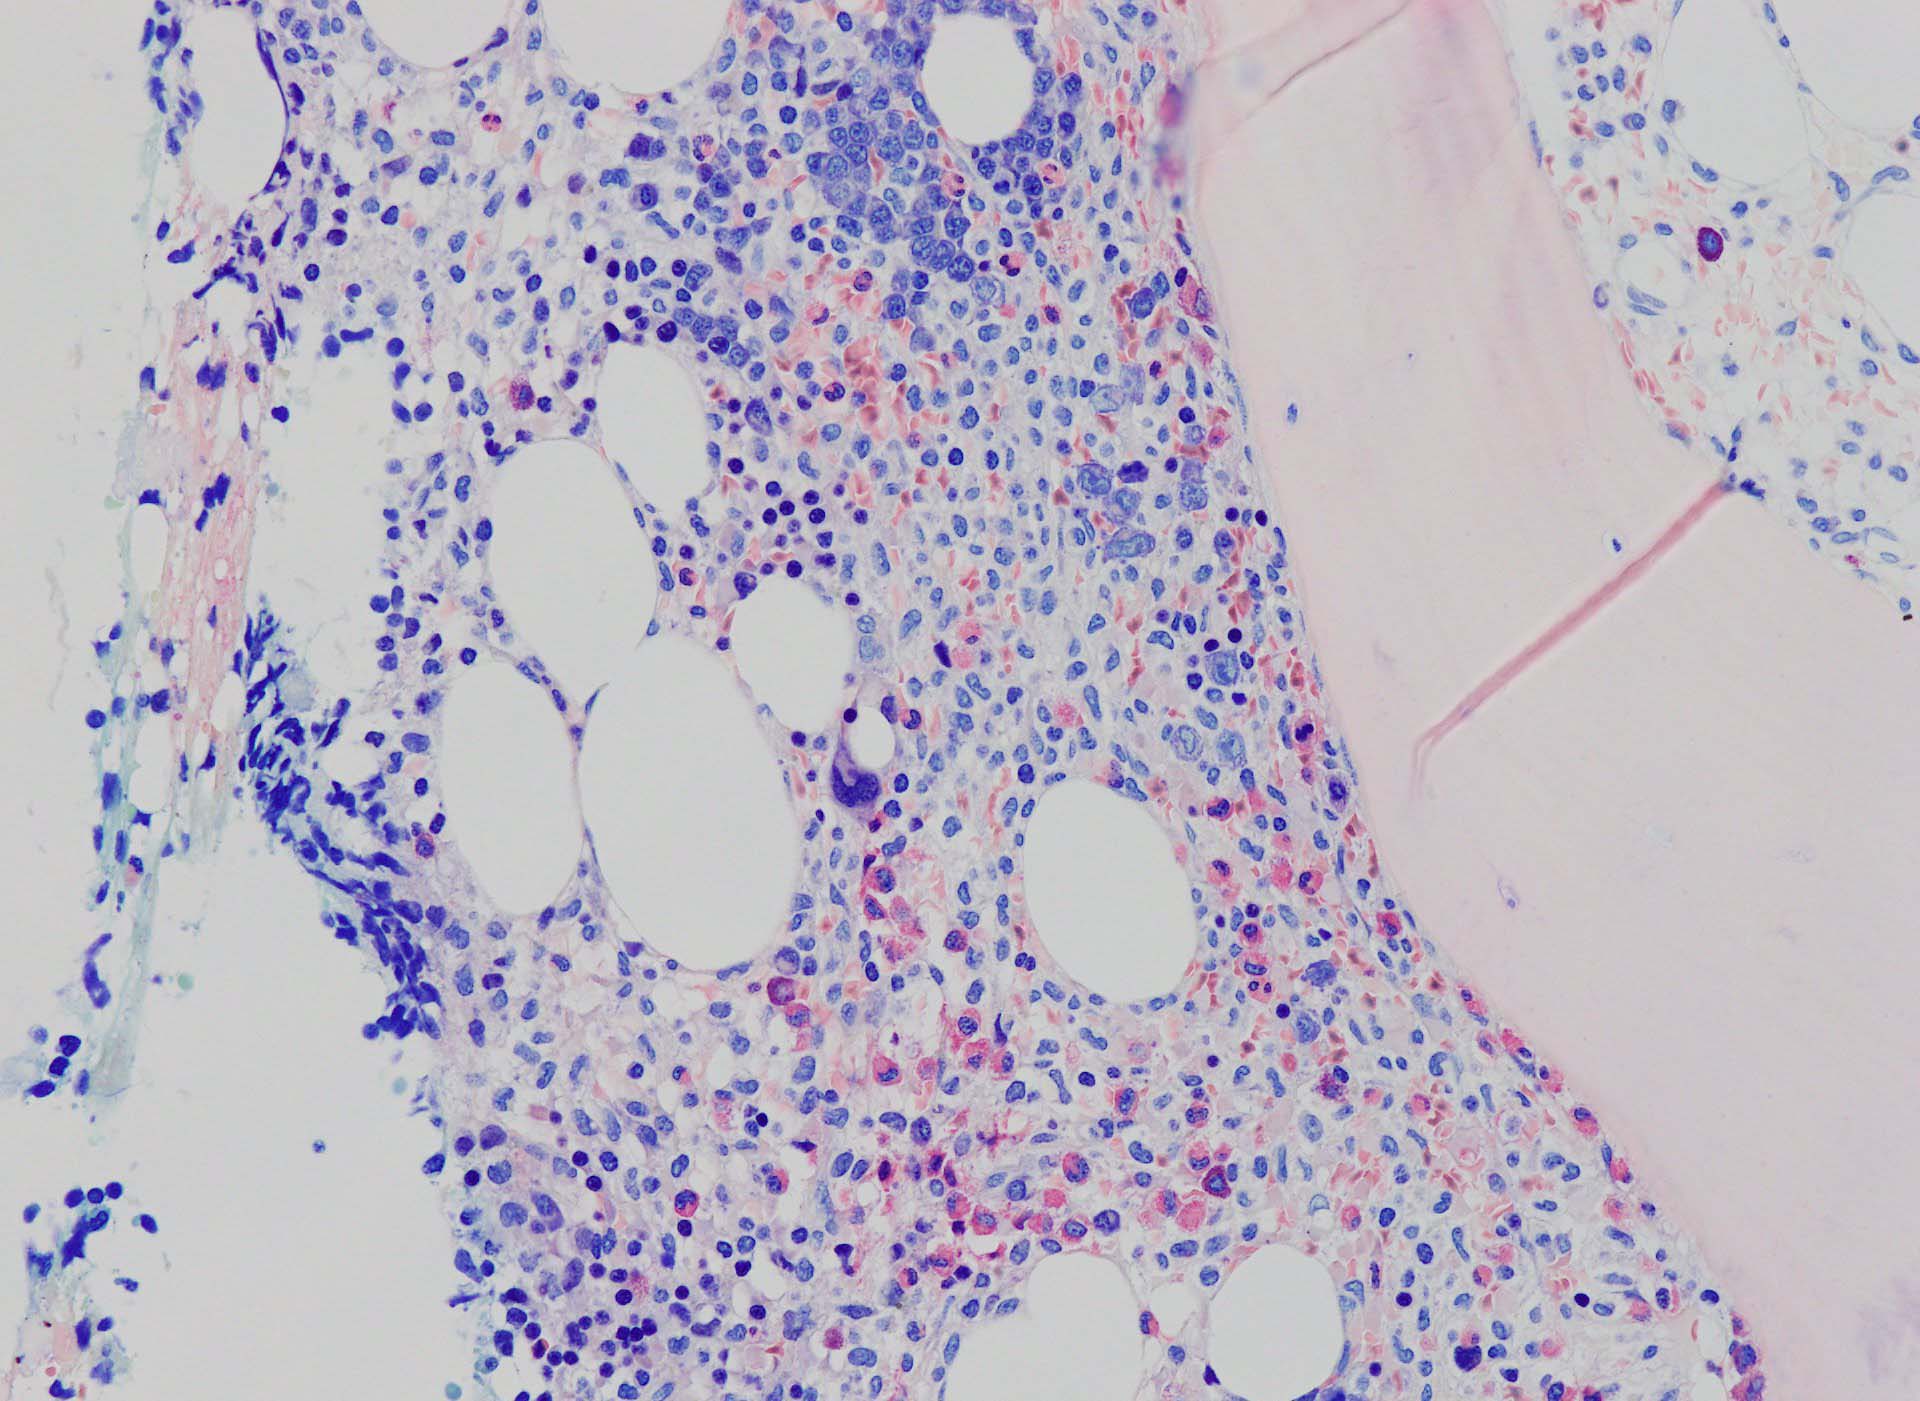

bone marrow trephine biopsy: dry tapのため骨髄生検が行われる. cellularityは40-80%とhypercellular marrow. 流れのある細胞配列は線維化を疑わせる.

ASD-G 低倍率所見では赤芽球血島は幼若赤芽球の集簇巣が散在する, 顆粒球系細胞(ASDに赤く染色される)は減少,granulopoietic hypoplasiaを呈する.疎な集簇を示すmast cellsの増加がある.

ASD-G陰性の細胞がびまん性に増加しているように見える.

ASD-Giemsa陰性の細胞がシート状に増殖する. 核はクロマチン濃染, 核小体は不明瞭.類円形, 卵円形, くびれを持つ多稜形核, 長円形いびつで屈曲した核, など多彩. 細胞質は淡清色調, 広く淡明. 赤芽球血島は幼若赤芽球のみで形成される異形成像を示す. やや離れて成熟赤芽球が疎な集簇を示す.

Ag染色では, 疎な弾性線維が増生し,増殖細胞を小胞巣状に分画するいわゆる「lymphomatoid pattern」を呈する. 本例では, Mgkに異形成所見がある.